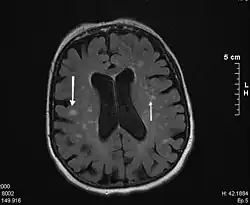

Bild einer Magnetresonanztomographie

Die Diagnose wird mit einer MRT (Magnetresonanztomographie = Kernspintomographie) gesichert. Diese zeigt in den T2-gewichteten Bildern typische weißliche konfluierende Herde um die Ventrikel und besonders an den vorderen und hinteren Enden der Seitenventrikel eine kappenartige Sklerosezone.